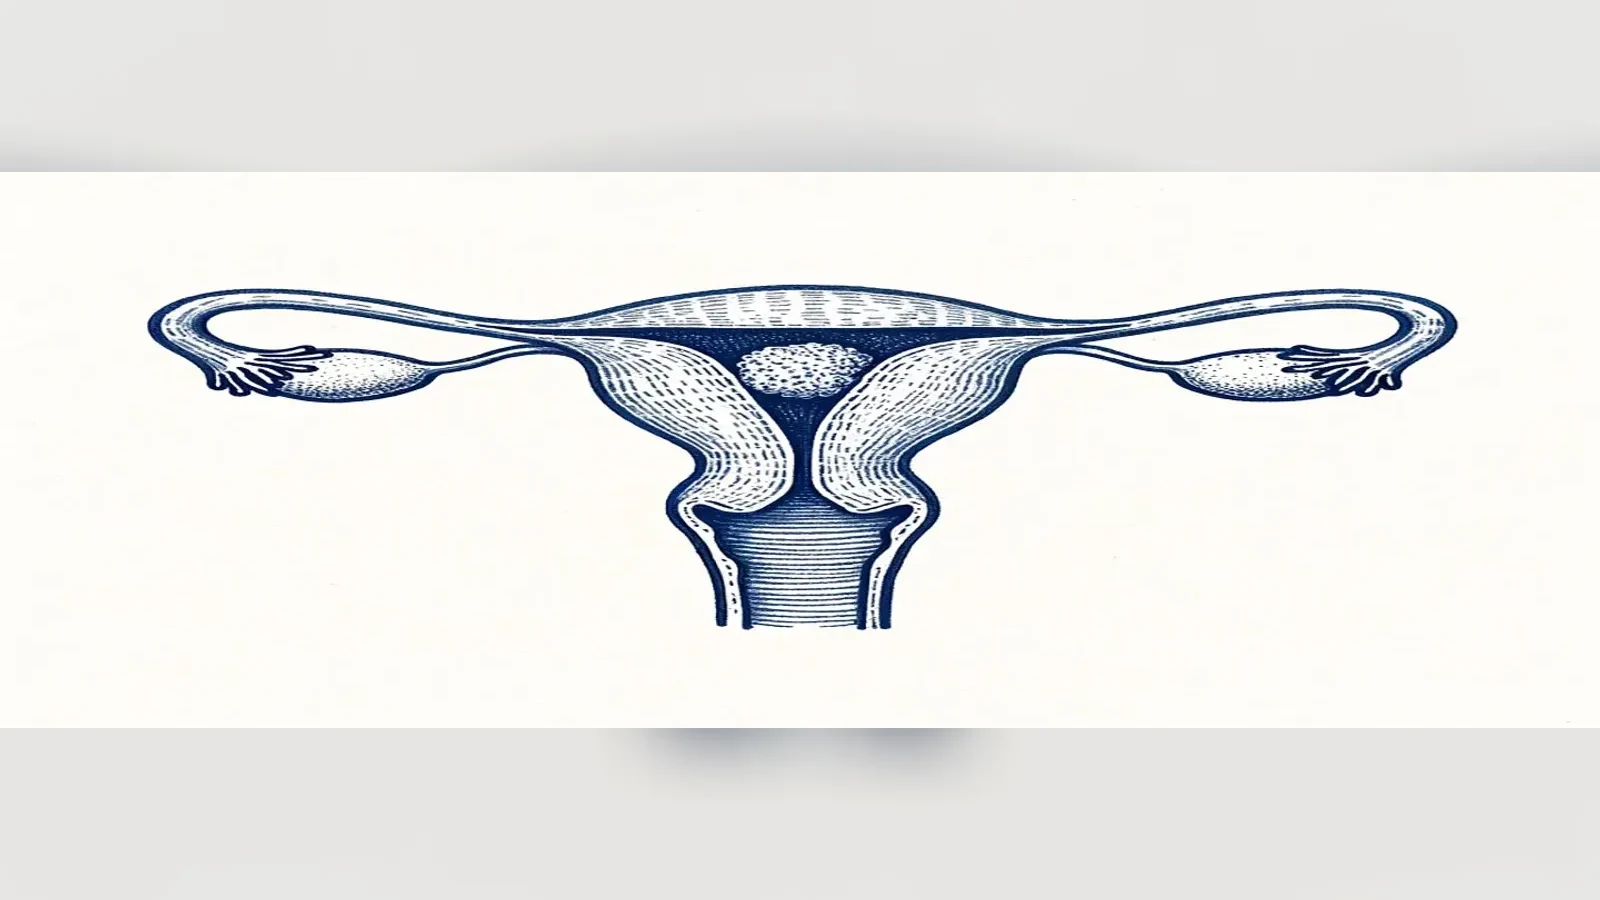

Endometrium Kalınlığı ve Tüp Bebek: Rahim Zarı Kaç mm Olmalı?

Endometrium kalınlığı tüp bebekte önemli bir takip ölçümüdür; ancak transfer kararı yalnızca milimetre değerine göre verilmez. 7 mm eşiği, ince endometrium nedenleri ve tedavi seçenekleri kanıta dayalı olarak değerlendirilmelidir.